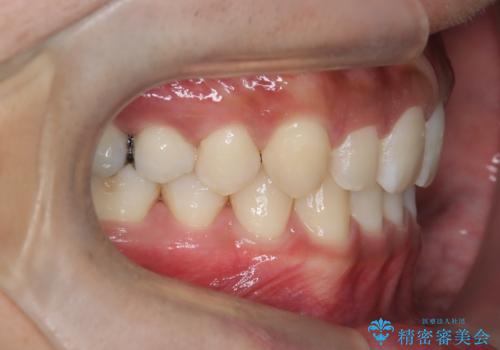

【インビザライン】空隙歯列の矯正

- 前歯の隙間を主訴に来院されました。

なるべく目立たない治療を希望されましたので、インビザラインにて治療を行なっております。

単純に前歯の隙間の閉鎖をしてしまうと、前歯に早期接触が生まれ、臼歯が噛まなくなってしまいます。適切な治療計画を立てることで、噛み合わせも良好な結果を得ることができました。